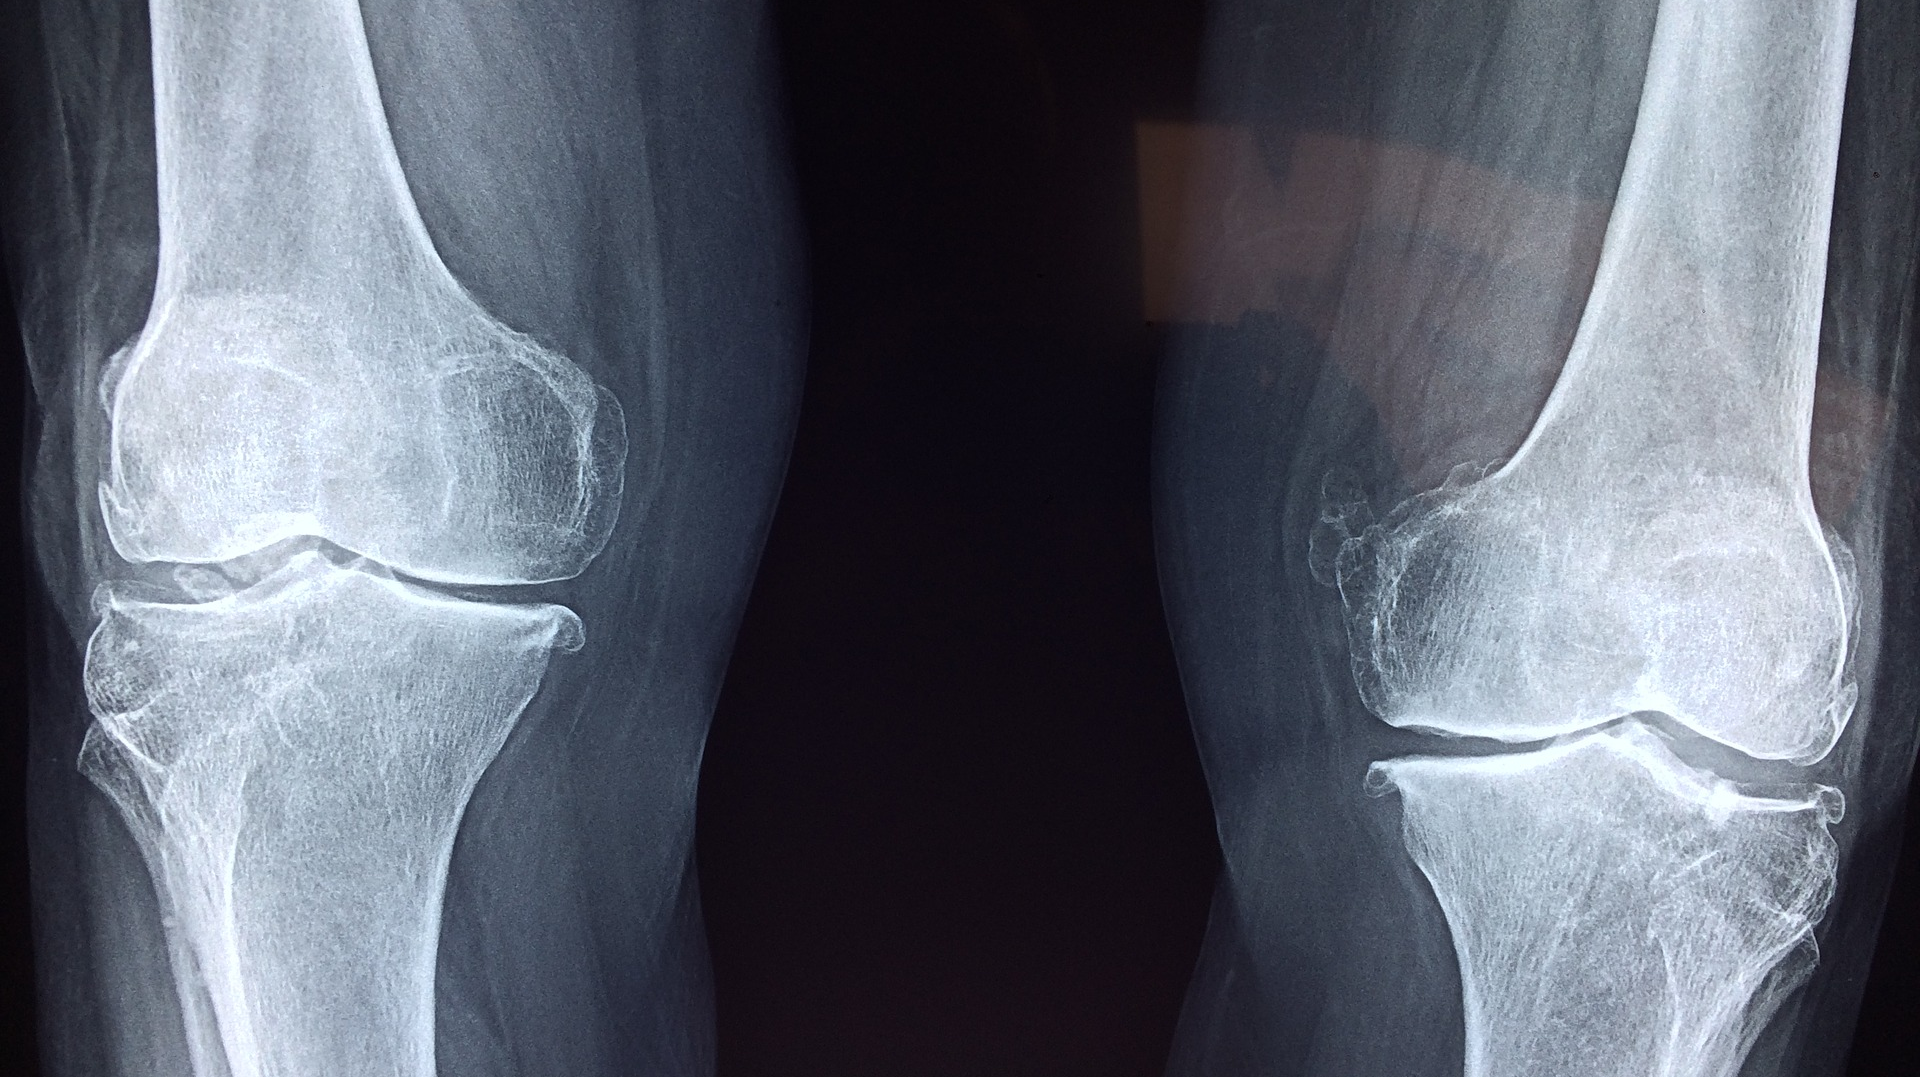

Potential complications of joint replacement include scarring, inflammation, blood clots and infections. If an infection occurs, it can lead to pain, redness, swelling and decreased joint function and potentially require antibiotics and revision surgery to treat the infection and install a new prosthetic implant. Physicians typically evaluate for potential infections using X-ray images or laboratory analysis of joint fluid, which can take days for results.